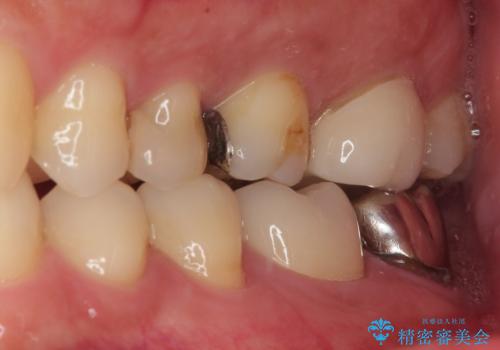

- 歯の間に物が詰まるとのことで来院された患者様です。以前に歯冠部の神経の一部を取り除き、MTAセメントという特殊なセメントを充填し、歯根部の神経を温存する生活歯髄療法(VPT)を行われておりセラミックの詰め物にて修復されていました。セラミックの詰め物が少し欠けたことにより食べ物が挟まってしまう状況でした。

まず神経の生活反応を確認し、今回はセラミックの詰め物のやり替えではなく、セラミックのかぶせ物で治療を行っていくこととしました。

拡大鏡視野下で、セラミックの詰め物、虫歯の除去を行い、オールセラミッククラウンに適した形に整えました。

見た目、機能面ともに満足していただけました。